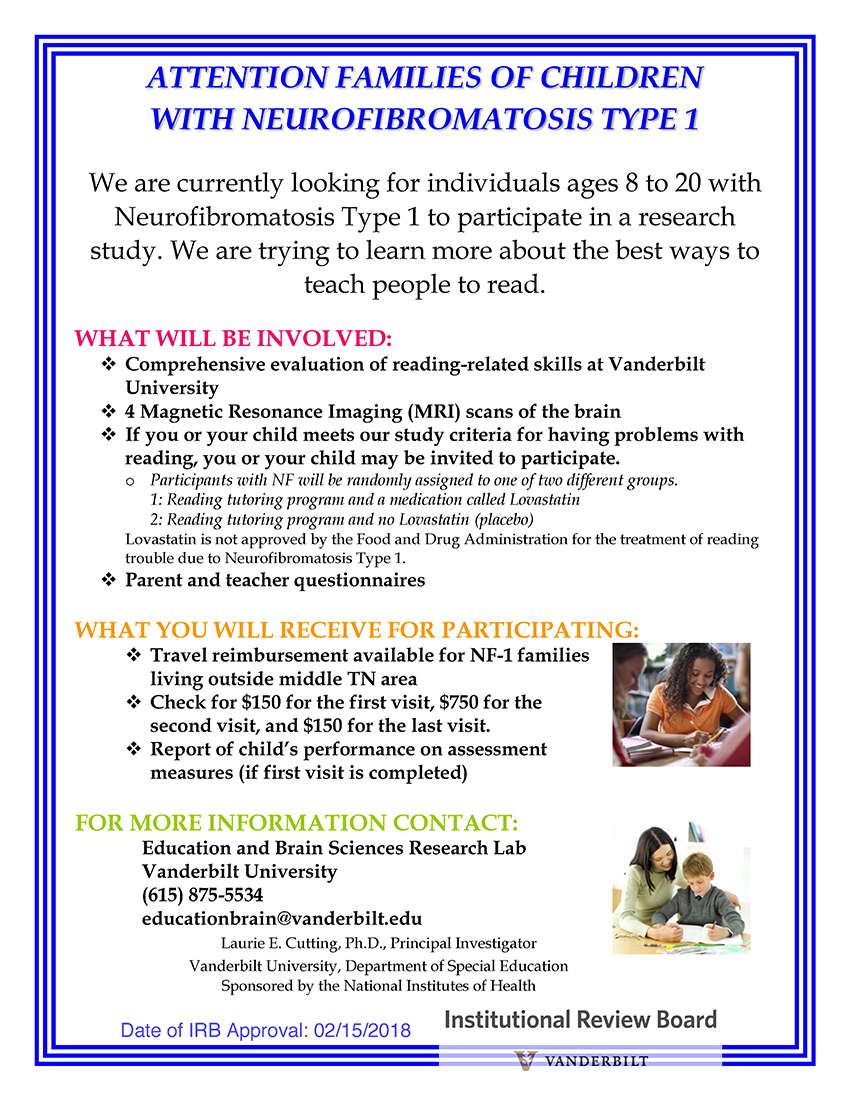

- Individuals age 8–20 with clinical diagnosis of NF1 (neurofibromatosis Type 1) and known or suspected reading difficulties

Study recruitment will be ongoing for the next three and a half to four years, providing funding continues. The study, which will last about 26 weeks, involves an initial phone screening to determine eligibility, lab visits at Vanderbilt, intensive reading interventions, MRI scans and, for some participants, an investigational study medication. Participants will be compensated up to $1,050, in addition to travel reimbursement for families living outside Middle Tennessee.

The goal of the study is to determine the best ways in which people with neurofibromatosis Type 1 who struggle with reading can learn to become good readers. The principal investigator of the study is Laurie Cutting, Patricia and Rodes Hart Professor of Special Education at Peabody College, professor of pediatrics in the Vanderbilt School of Medicine, and associate director of the Vanderbilt Kennedy Center.

Please see the two flyers below for more detailed information about the study.